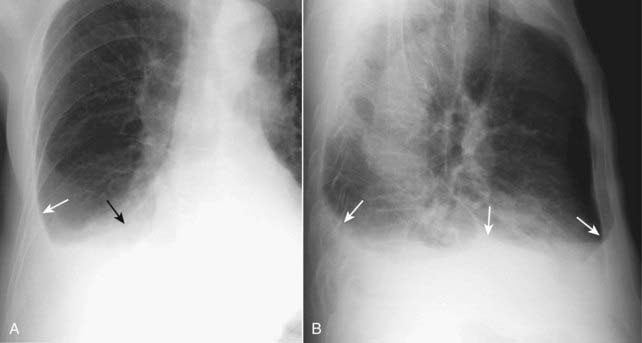

Figure 6-14 Hydropneumothorax, frontal (A) and lateral (B) projections.

Unlike pleural effusions alone, whose meniscoid shape is governed by the elastic recoil of the lung, hydropneumothorax produces an air-fluid level in the hemithorax (solid black arrows in A and solid white arrows in B) marked by a straight edge and a sharp, air-over-fluid interface when the exposure is made with a horizontal x-ray beam. Surgery, trauma, a recent thoracentesis to remove pleural fluid, and bronchopleural fistulae are among the causes of a hydropneumothorax. This person was stabbed in the right side. This actually represents a hemopneumothorax, but conventional radiography is unable to distinguish between blood and any other fluid. A pleural tap might be necessary to better define the pleural fluid.